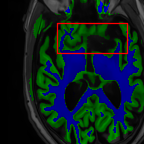

Sparsity LI 2D CNN 3D CNN Ours GT

4 Refer to caption (a) 0.6787/0.7972 Refer to caption (b) 0.8143/0.8776 Refer to caption (c) 0.8190/0.8714 Refer to caption (d) 0.8664/0.9085 Refer to caption (e) GM/WM

Refer to caption (f) 0.6808/0.7161 Refer to caption (g) 0.8103/0.8631 Refer to caption (h) 0.7950/0.8606 Refer to caption (i) 0.8598/0.9115 Refer to caption (j) GM/WM

8 Refer to caption (k) 0.5139/0.7240 Refer to caption (l) 0.6619/0.8224 Refer to caption (m) 0.6878/0.8584 Refer to caption (n) 0.7798/0.8853 Refer to caption (o) GM/WM

Refer to caption (p) 0.5910/0.6947 Refer to caption (q) 0.6516/0.8021 Refer to caption (r) 0.6507/0.8186 Refer to caption (s) 0.7471/0.8540 Refer to caption (t) GM/WM

Figure 6: Visual comparison of gray matter (Green)/white matter (Blue) segmentation over different methods, with respective DICE scores listed under the images.

In Fig. 6, we demonstrate the advantage of the proposed method in brain matter segmentation. It is clear that although 2D and 3D CNN generates visually plausible interpolation as presented in Fig. 5, the brain matters are easily misclassified due to incorrect anatomical structures and blurred details.